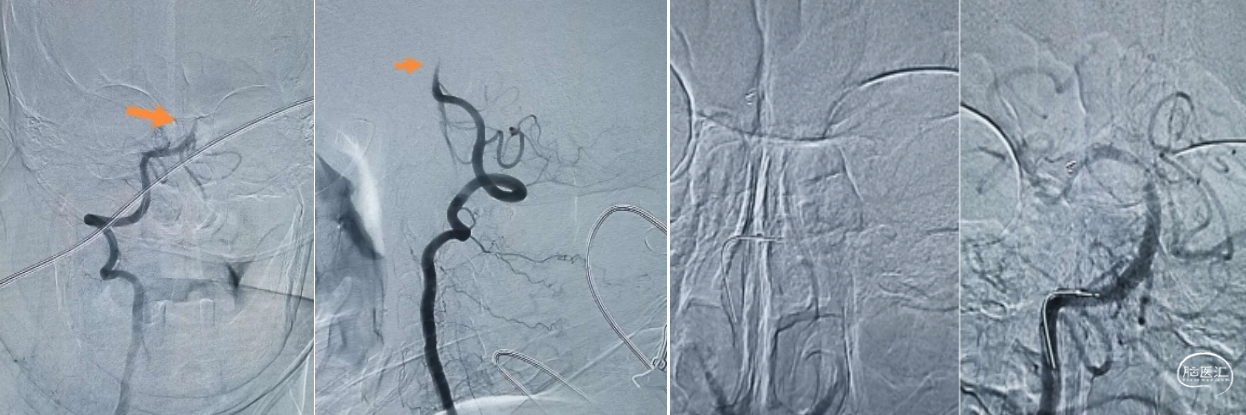

二、经桡动脉入路中间导管通路基底动脉取栓

病史介绍:

患者:患者女性,68岁,“间断心悸、胸闷4月再发3小时”入院,烦躁问话不答,四肢无力。既往高血压病史,血压达160/?mmHg,有冠心病病史,否认糖尿病。

查体:BP:158/78mmHg,烦躁,不完全混合型失语,查体不合作,心律齐,四肢肌力不肯定,四肢无自主活动,双侧巴氏征阳性。造影示:基底动脉闭塞。

手术分析:

闭塞部位:基底动脉闭塞。

入路选择:左侧椎动脉起始狭窄,右椎通畅可采用右侧桡动脉入路。

麻醉选择:后循环全麻防止患者躁动。

材料选择:直接使用中间导管。

手术材料:6F桡动脉鞘、颅内支持导管 5F 125cm银蛇、0.021"微导管、0.014微导丝、通桥蛟龙 3*15(小支架)4*20mm、50ml卡口注射器或自制卡口注射器。

手术操作:

1、全麻下桡动脉入路:利用超滑导丝交换技术直接送入5F中间导管(下图1)。

2、中间导管到位造影基底动脉闭塞,向左侧椎动脉返流(下图3)。

3、微导管造影:微导管位于真腔,右侧大脑后动脉P3段(箭头所指)闭塞(下图2、4)。

4、支架释放:4*20取栓支架送入后可见血流通畅,左侧大脑后动脉仍闭塞。取栓后基底动脉通畅大脑后动脉P3段闭塞(下图5)。

决定取栓,微导丝通过,少量血流通过,血栓(箭头所指)更加明显了,回撤支架后造影:血流通畅,血管痉挛解除。

对于本次病例直接中间导管建立通路,中间导管到位造影基底动脉闭塞,4*20mm支架基底动脉取栓,小支架3*15mm大脑后动脉钳夹取栓。3*15mm小支架对血管刺激性更小,取栓术后血流通畅,未出现与支架相关并发症,且一把拉通,是远端血管取栓的一个选择。